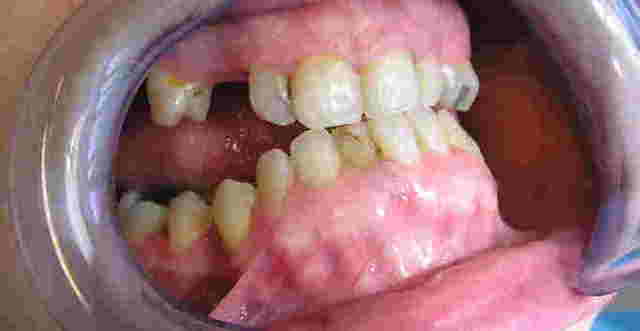

Patiente, environ 30 ans,reçue cette semaine, avec pour motif de consultation une réhabilitation complète de sa bouche + motif esthétique.

Quelques soins à réaliser, ce qui n'est pas un problème, par contre l'occlusion est particulièrement étrange.

Elle se positionne spontanément comme sur les 1ères photos, et je n'ai pas pu la manipuler plus en arrière. En articulé inversé, je retrouve une hauteur normale mais cette position lui cause des douleurs aux ATM.

Claquements bilatéraux aux niveaux des ATM, et un trajet de fermeture en baillonette avec décrochement à droite.

Sur la pano on retrouve cette drôle de mandibule... Infra alvéolie molaire et supra incisive...

Bonjour,ce qu'il est intéressant de noter, c'est l'aspect des procès alvéolaires, qui sont assez marqués et le fait que tu n'as pratiquement plus de calage occlusal postérieur avec en corollaire une propulsion mandibulaire pour aller mastiquer sur quelque chose.

Apparemment elle était en classe III.

La position qu'elle adopte spontanément est le bout à bout de la photo 1.

Je ne voudrai pas te contrer mais pour ce qui est de l'interposition linguale; sur la photo 1 on voit bien la langue qui déborde sur les dents postérieures restantes.

Pour ce qui est de la DV, il y a une raison pour laquelle elle adopte la position 1.